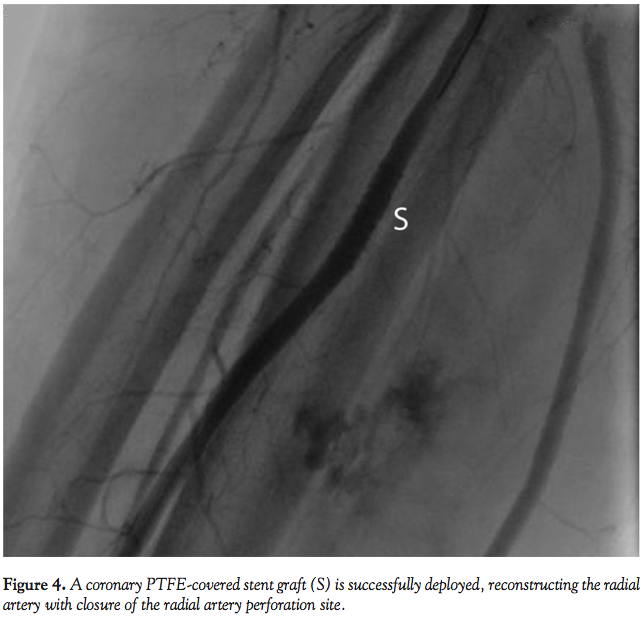

Abbott Vascular) was undertaken at 8 atm of pressure for 500 seconds (Figure 3). Despite these measures, persistent extravasation of dye was noted, along with arm pain and hematoma expansion. A coronary polytetrafluoroethylene (PTFE)-covered stent graft (JoStent Graftmaster, 4.00 mm diameter, 19 mm length; Abbott Vascular) was placed at the site of the radial artery perforation to obtain hemostasis (Figure 4). Following successful deployment of the covered stent graft at the site of the radial artery perforation, no extravasation of contrast dye was noted. The patient was admitted to the coronary care unit and monitored for the development of compartment syndrome. At 2 week follow-up, the hematoma had resolved.